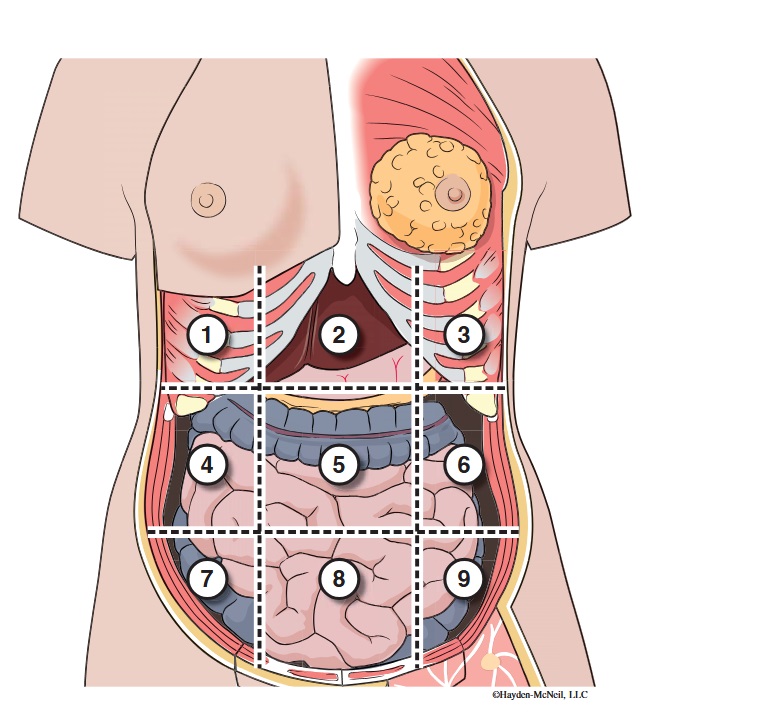

What abdominal region is labeled #1?

right hypochondriac

What abdominal region is labeled #2?

epigastric

What abdominal region is labeled #3?

left hypochondriac

What abdominal region is labeled #4?

right lumbar

What abdominal region is labeled #5?

umbilical

What abdominal region is labeled #6?

left lumbar

What abdominal region is labeled #7?

right iliac/ inguinal

What abdominal region is labeled #8?

hypogastric

What abdominal region is labeled #9?

left illiac/ inguinal

What organs are apart of the right hypochrondriac region?

right lobe of liver, gallbladder, right adrenal gland

What organs are apart of the epigastric region?

pyloric end of stomach, duodenum, pancreas

What organs are apart of the left hypochondriac region?

stomach, spleen, left adrenal gland

What organs are apart of the right lumbar region?

ascending colon, right kidney, portion of small intestine

What organs are apart of the umbilical region?

omentum, mesentery, small intestine

What organs are apart of the left lumbar region?

descending colon, left kidney, portion of the small intestine

What organs are apart of the right iliac/ inguinal region?

cecum of large intestines, appendix, right ovary

What organs are apart of the hypogastric region?

ileum, bladder, uterus

What organs are apart of the left iliac/ inguinal region?

sigmoid colon, left ureter, left ovary